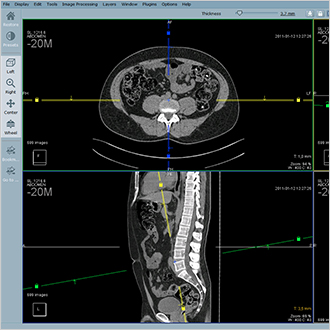

Hyper.PACS

HyperPACS è un sistema PACS universale per tutte le immagini medicali, sia DICOM che non DICOM. Si fonda su tre pilastri: velocità, stabilità e sicurezza. Hyper.PACS consente accesso rapido ai dati, stabilità e protezione dei dati al 100%.

L'interfaccia è stata sviluppata in collaborazione con gli utenti affinché risultasse intuitiva per la diagnosi, la visualizzazione e la telemedicina. Il flusso di lavoro è ottimizzato grazie a protocolli di visualizzazione personalizzati, visualizzazione della cronologia e sospensione della sessione.

Sono inoltre disponibili moduli aggiuntivi, come la pianificazione ortopedica e lo scambio di immagini di telemedicina.